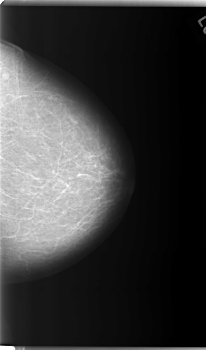

C_0086_1.RIGHT_MLO

RIGHT_MLO LINES 5904 PIXELS_PER_LINE 3600 BITS_PER_PIXEL 12 RESOLUTION 50 OVERLAY

FILE: C_0086_1.RIGHT_MLO.OVERLAY

TOTAL_ABNORMALITIES 1

ABNORMALITY 1

LESION_TYPE MASS SHAPE LOBULATED MARGINS MICROLOBULATED

ASSESSMENT 5

SUBTLETY 5

PATHOLOGY MALIGNANT

TOTAL_OUTLINES 1

BOUNDARY